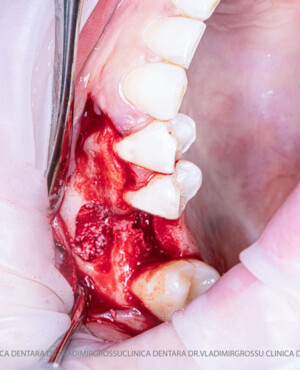

Stomatologia estetică reprezintă în prezent una dintre direcțiile principale de specializare a medicilor clinicii Dr. Grossu din Chișinău.Adiția sau augmentarea osoasă este o procedură chirurgicală prin care se refac defectele osoase rezultate în urma extracțiilor dentare, bolii parodontale sau traumelor dento-alveolare.

După extracția dentară, în intervalul de 6-12 luni, osul alveolar suferă un proces natural de remodelare, ceea ce conduce la scăderea volumului osos prin rezorbție. De aceea, inserția implantului dentar este ideală imediat după extracție sau, cel târziu, în primele 3-4 luni după aceasta.Scopul procedurilor de adiție osoasă este refacerea fundației osoase necesare pentru stabilizarea corectă a implantului dentar. Pentru ca un implant să reziste în timp la forțele masticatorii, este nevoie de o bază osoasă solidă și sănătoasă.